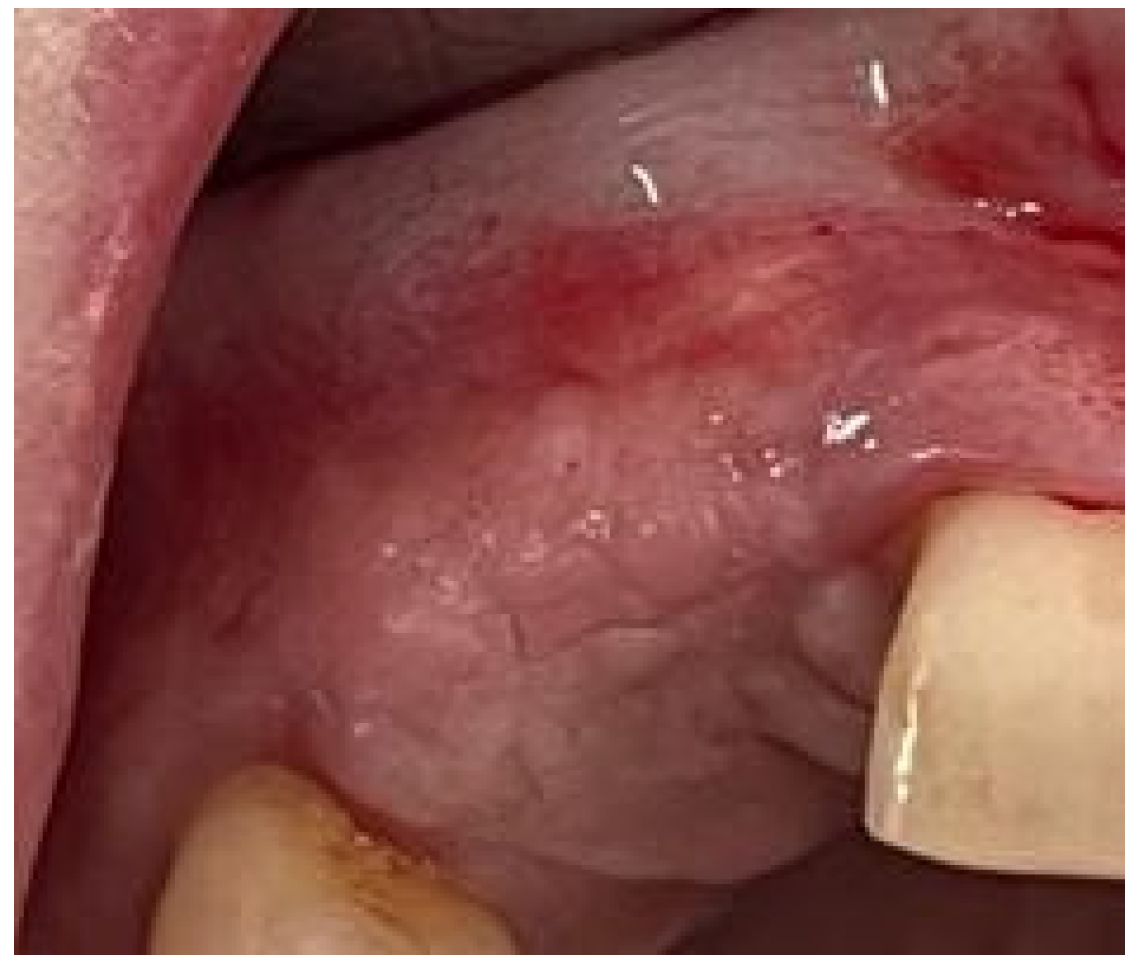

2. Case Presentation